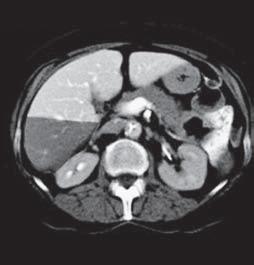

Kazuistika I (segmenty jaterní tkáně)